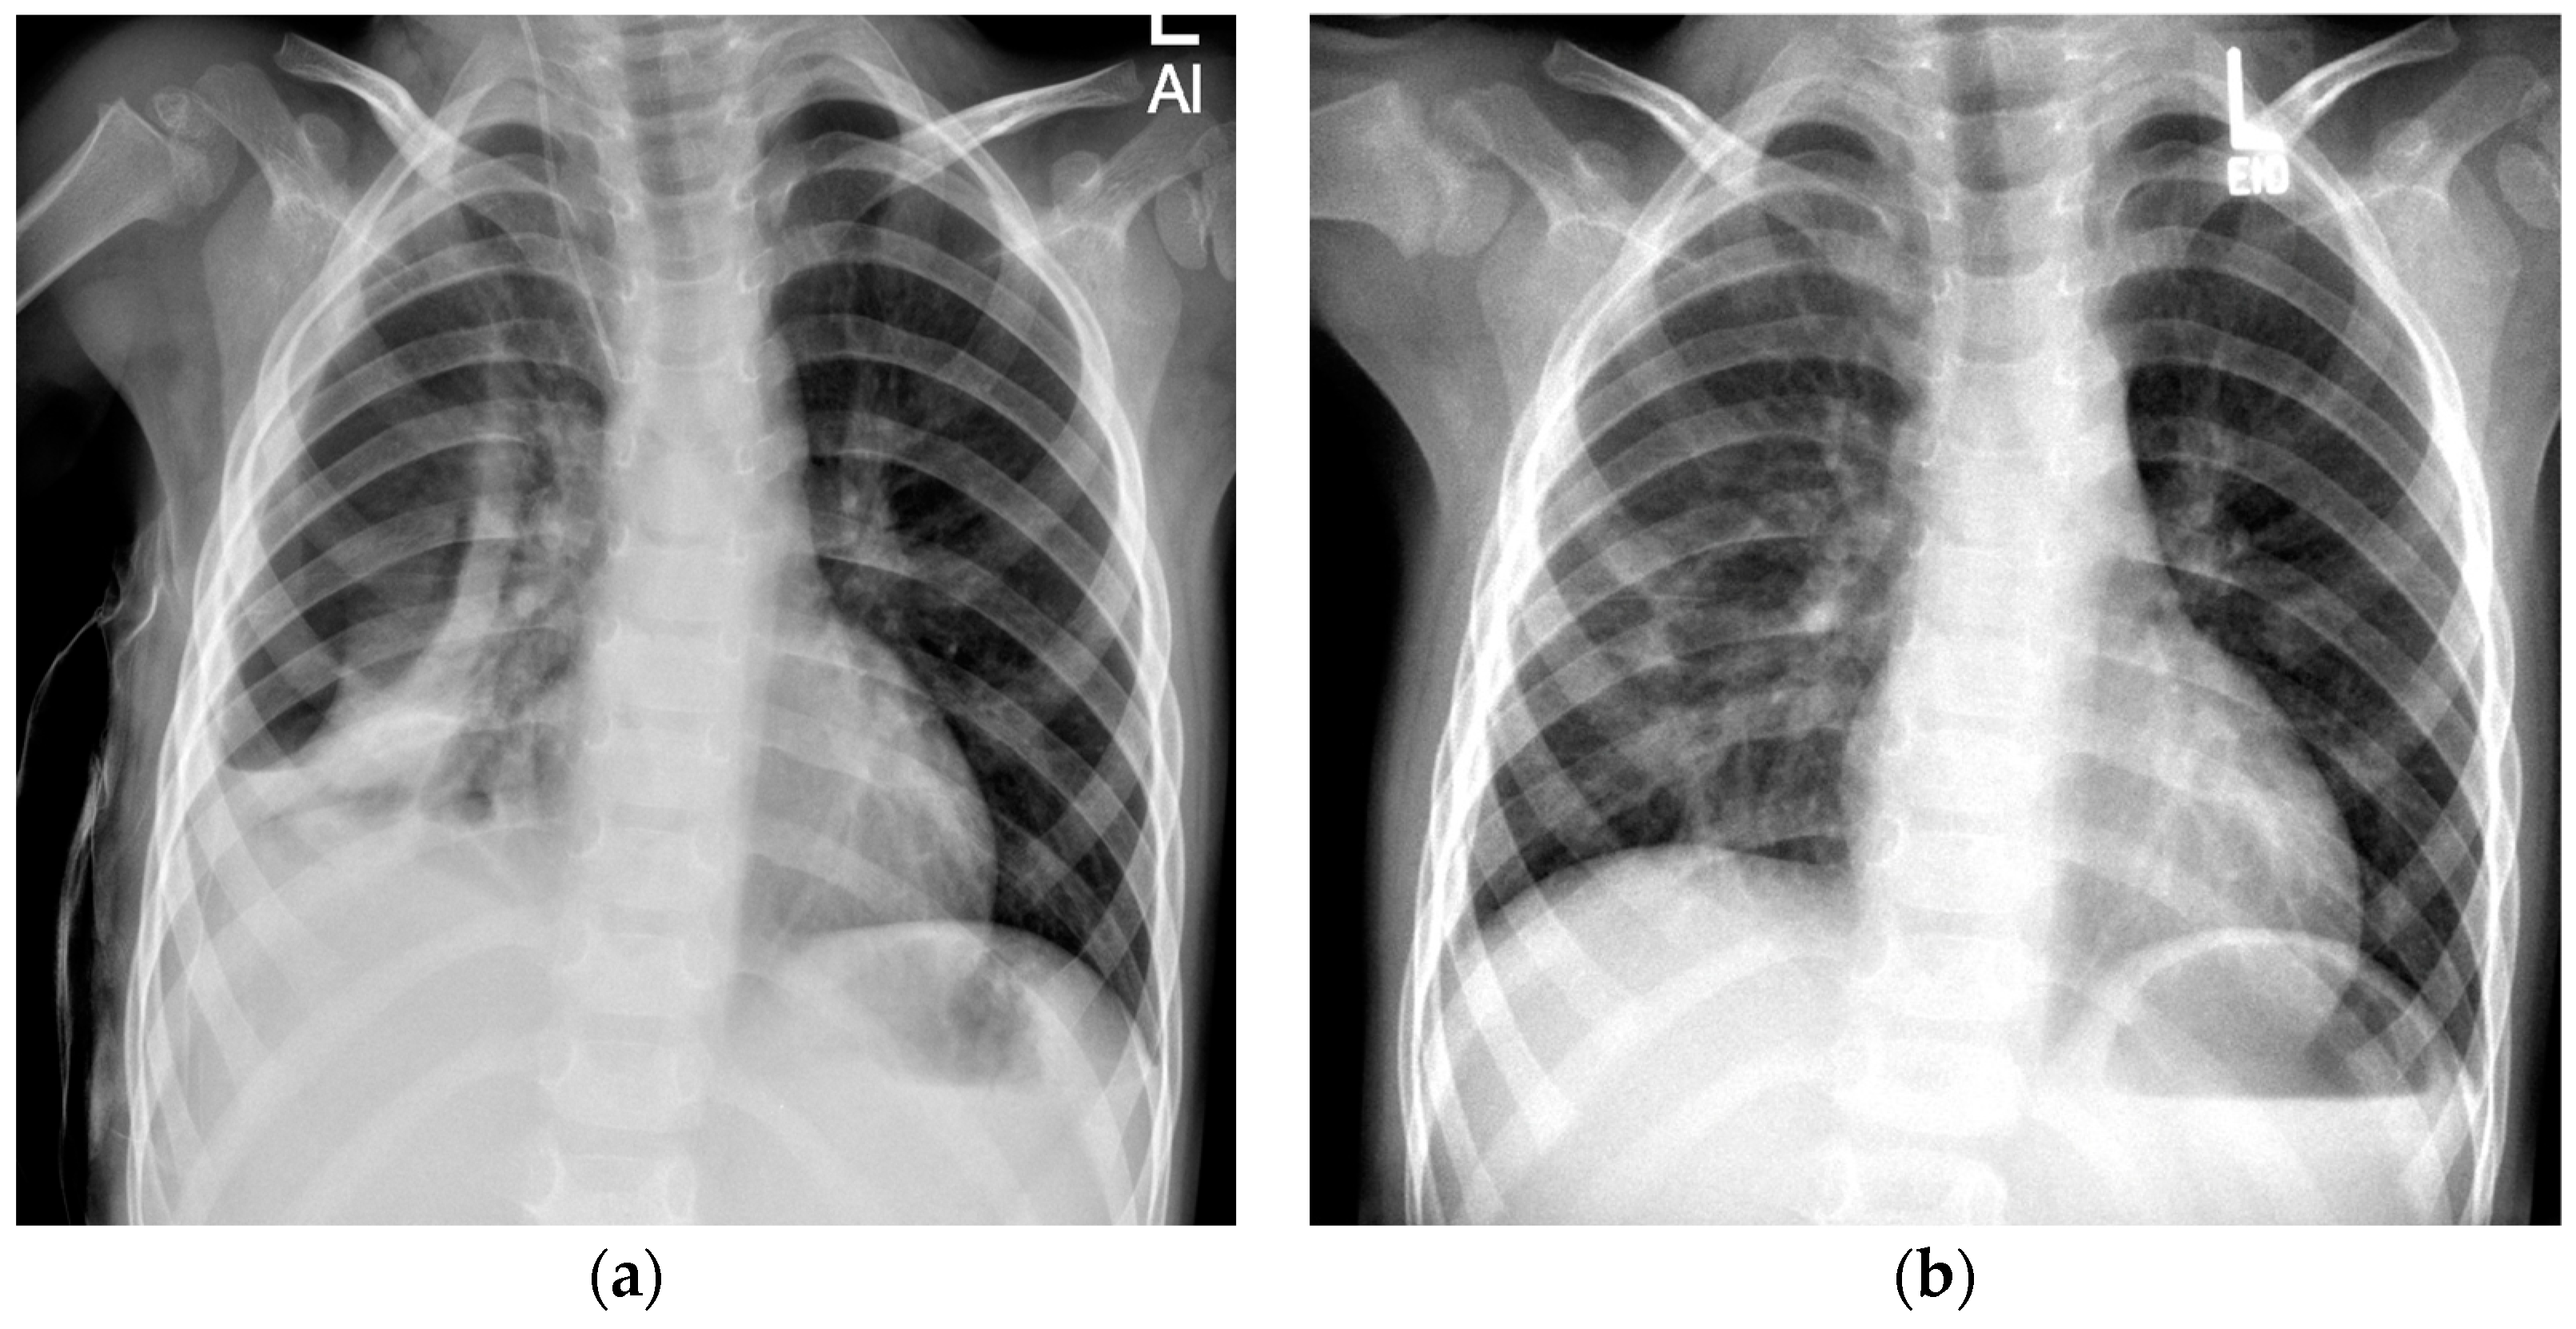

At the end of our FU, three patients showed to have a “pneumothorax ex vacuo”. It should be noted that one of the two patients with a “pneumothorax ex vacuo” at the end of our FU period was immunosuppressed due to liver transplantation for progressive familial intrahepatic cholestasis. After discharge from our inpatient treatment, there was no renewed X-ray control, although the patient was regularly treated due to his underlying disease. The second patient was also not subjected to an X-ray during the follow-up period. Instead, a clinical and sonographic examination was performed.

The third patient with a “pneumothorax ex vacuo” was transferred to the UKE from an external hospital. At the time of transfer, the patient had been symptomatic for 11 days and was receiving intravenous antibiotic therapy. After transfer, a pleural drain was initially inserted, which had to be revised the following day due to dislocation. In the course of the procedure, the drain was pulled accidentally, resulting in a progressive pneumothorax, so that VATS was performed and the drain was reinserted. Therefore, this patient had three thoracic interventions. After the patient was discharged, there were a total of three follow-up radiological examinations within 3 weeks, which still showed a detectable but regressive “pneumothorax ex vacuo”. After the last follow-up, the patient returned to her home country and was not available for further follow-up (Figure 4). It is important to highlight that the FU period for these two patients was shorter than our average follow-up period, and with a longer follow-up period detection of spontaneous reabsorption of the pneumothorax might have been seen in these cases as well.

Figure 4. “Pneumothorax ex vacuo” in a 2-year-old girl. (a) Anterior–posterior (AP) chest radiograph taken 2 days after discharge showing a left-sided pneumothorax (arrow). (b) Persistent pneumothorax 7 days after discharge. (c) At 2.5 weeks, pneumothorax is still radiologically detectable.